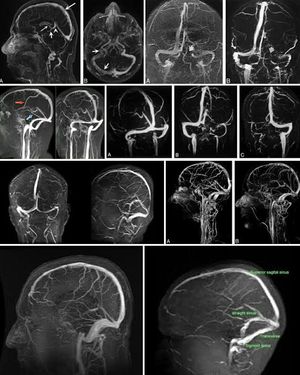

MRV is used to assess abnormalities in venous drainage of the brain . 2-dimensional (2D) time-of-flight (TOF) MR venography (MRV) and 3-dimensional (3D) phase-contrast (PC) are the technique commonly used to assess the cerebral venous sinuses because they are easy to perform and do not require contrast administration.